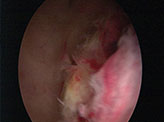

Since the ultrasound features were not typical of molar changes, she was subjected to an operative hysteroscopy, after arranging blood. Hysteroscopy was carried out. Using a 26 Fr resectoscope , a yellowish white tissue mass seen in the posterior wall, was resected ,with wire loop, using bipolar current and sent for histopathological examination{Image 1 and 2}.